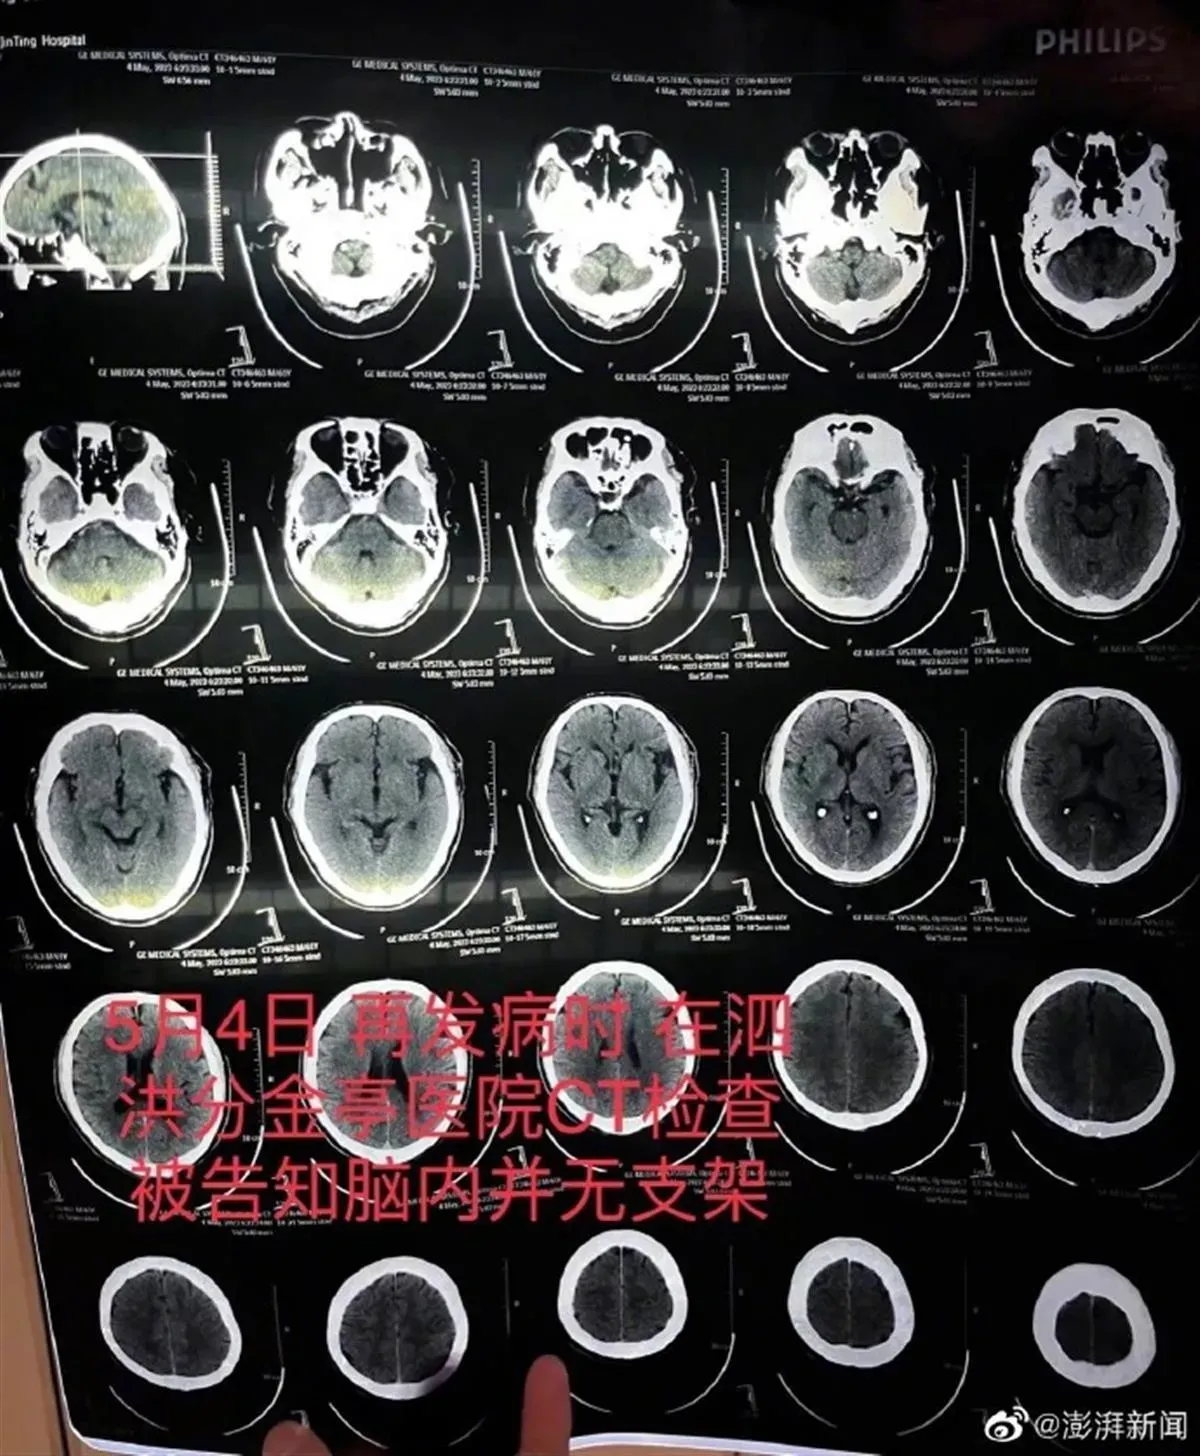

朱父在泗洪縣分金亭醫院的CT檢查報告,顯示顱內並無支架。(圖/翻攝澎湃新聞)

不料一個月後,5月4日朱父突發嚴重腦中風,被救護車送至江蘇省宿遷市泗洪縣分金亭醫院搶救,家屬沒想到的是,當時CT檢查發現,其顱內段部分動脈已嚴重堵閉,同時未發現此前植有支架。